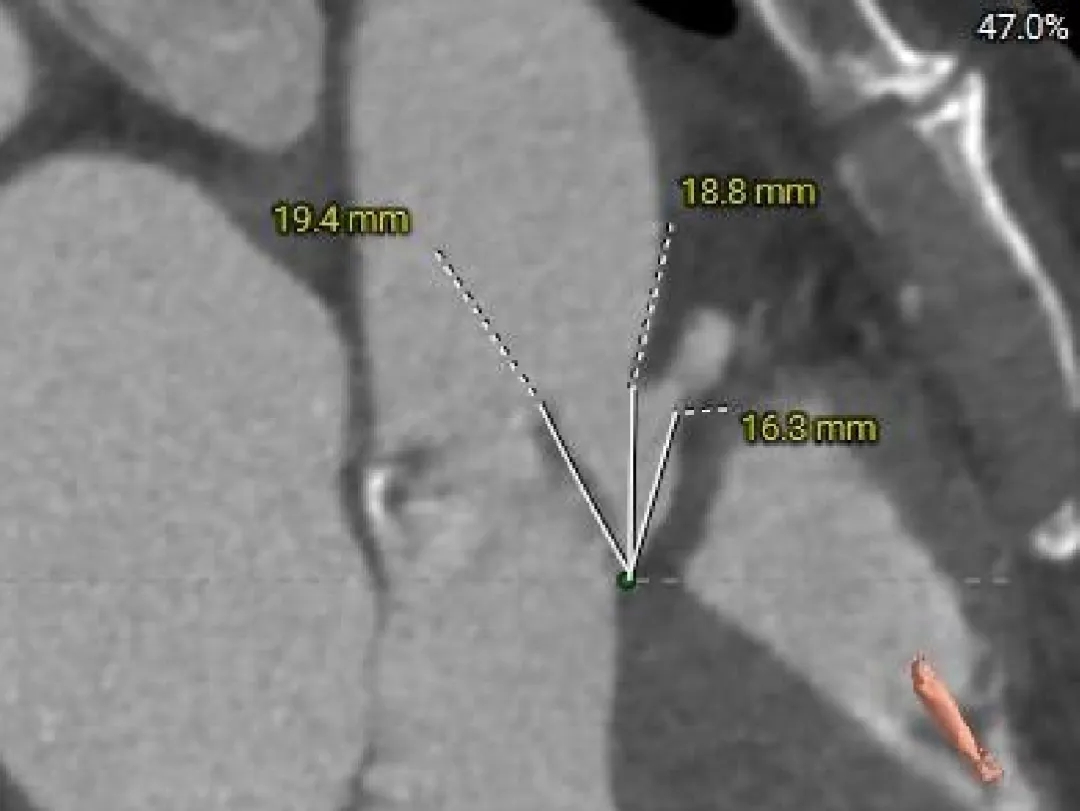

Right Coronary

17.1mm

RCA & Leaflet

16.3mm<19.4mm

-

双侧冠脉开口高度可

左、右冠瓣叶长度>冠脉开口下缘到根部距离

结合SOV、STJ测量,窦部空间较小,预估冠脉阻挡风险较高